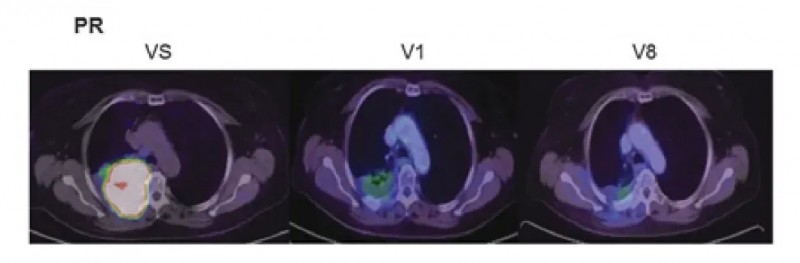

2、部分缓解(PR)病例:INT组(NK细胞+同步放化疗)另1例PR患者,基线检查(VS)时右肺存在较大肿瘤肿块;至V8随访时,该肿块显著缩小,仅残留少量病灶,符合部分缓解(PR)标准。

▲图源“AACR”,版权归原作者所有,如无意中侵犯了知识产权,请联系我们删除